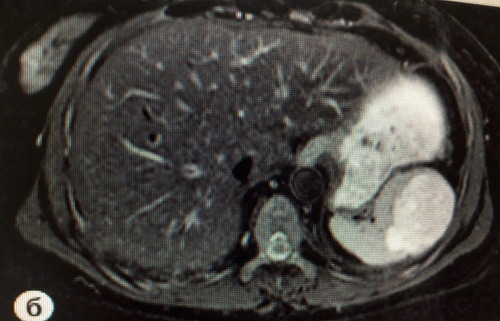

МРТ селезенки на снимках

МРТ снимок здоровой селезенки

МРТ снимок с патологией – опухоль